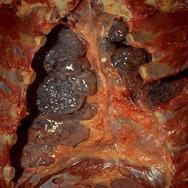

Особенно пагубно влияние алкоголя на печень, при длительном его употреблении развиваются хронический гепатит и цирроз печени. Алкоголь вызывает (в том числе и у лиц молодого возраста) нарушения регуляции тонуса сосудов, сердечного ритма, обмена в тканях сердца и мозга, необратимые изменения клеток этих тканей. Гипертоническая болезнь, ишемическая болезнь сердца и другие поражения сердечно – сосудистой системы вдвое чаще приводят к смерти у употребляющих спиртное, чем непьющих. Алкоголь оказывает вредное влияние на железы внутренней секреции и в первую очередь на половые железы; снижение половой функции наблюдается у 1\3 лиц, злоупотребляющих спиртными напитками. Алкоголизм существенно влияет на структуру смертности населения (рис. 5.2).

Рис. 5.1 Влияние алкоголя на организм человека